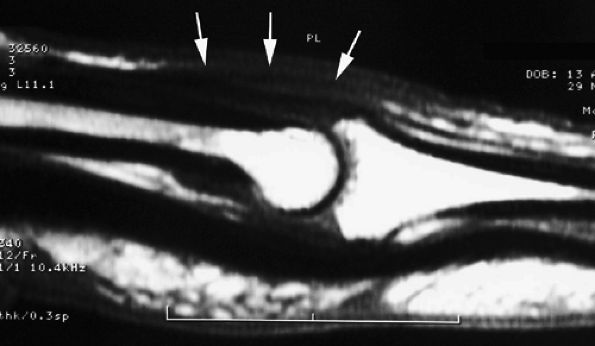

FIGURE 11.21 ● Sagittal T1-weighted images at the site of a volar plate injury of the PIP joint. The volar plate is absent. Note the associated injury of the dorsal capsule, which appears thickened (asterisk).

|